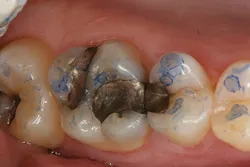

The clinical case in Figure 3 illustrates a patient who presented with a large, failing restoration containing cracks and decay. The patient was interested in an all-ceramic restoration. Occlusion was checked with articulating paper prior to treatment with a CAD/CAM restoration (figure 4). All previous restorative materials were removed from the tooth (figure 5). The tooth was restored using Grandio Core Dual Cure (Voco) build-up material (figure 6). A crown preparation was completed for a chairside CAD/CAM crown using the CEREC system (Dentsply-Sirona). The material of choice for this restoration was IPS e.max CAD (Ivoclar Vivadent), which is seen in Figure 7 after milling and in precrystallization form. The restoration was tried in and then polished, glazed, and placed in the oven for crystallization. The internal surface was then etched with 4.9% hydrofluoric acid, rinsed, and then coated with a silane coupler to create an optimal surface for bonding with the resin luting agent. The tooth was isolated and cleaned prior to etching. Once etched, the adhesive bonding agent (Futurabond U) was activated to mix the two liquids within the single-dose blister package. The blister seal was broken with the bonding agent brush and the adhesive was applied and agitated for 20 seconds. The adhesive was lightly dried for five seconds and then cured with an LED curing light for 10 seconds. A dual-cured adhesive resin luting agent (Bifix QM) was dispensed into the crown with its automix syringe (figure 8). The crown was seated and excess cement was removed after a two-second light cure. The tooth was then flossed and occlusion was checked (figure 9). The patient was very satisfied with the final result.

Figure 5: Teeth after all previous restorations have been removed